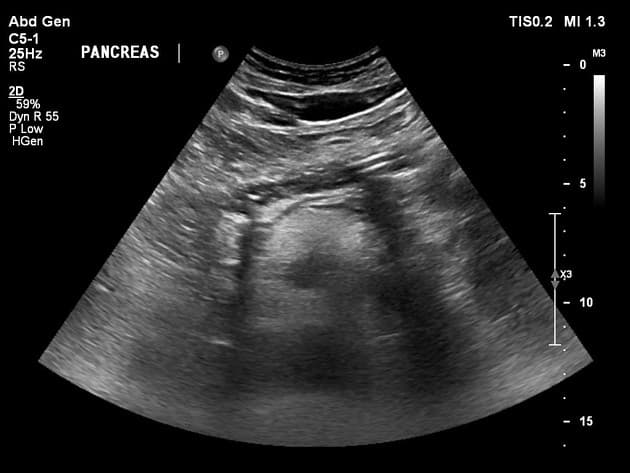

Multifocal focal fatty sparing in a steatotic liver

Gan to và tăng độ phản xạ âm thanh (echogenicity) lan tỏa.

Ít nhất ba vùng giảm âm (hypoechoic) dạng bầu dục, ranh giới rõ, ở thùy gan phải, chủ yếu liền kề hõm túi mật. Không phát hiện lưu lượng mạch máu nội tại trên Doppler màu.

THẢO LUẬN: Các hình ảnh học phù hợp với vùng gan không nhiễm mỡ khu trú đa ổ (multifocal focal fatty sparing) trong bối cảnh thoái hóa mỡ gan lan tỏa (diffuse hepatic steatosis). Trên siêu âm, các vùng này xuất hiện tương đối giảm âm so với gan thoái hóa mỡ xung quanh tăng âm và có thể bắt chước các tổn thương khu trú. Trên cộng hưởng từ dịch chuyển hóa học (chemical shift MRI), gan nền thể hiện giảm tín hiệu trên ảnh lệch pha, trong khi các vùng được bảo tồn thì không, phản ánh hàm lượng mỡ thấp hơn của chúng. Các vị trí điển hình bao gồm hõm túi mật và vùng quanh cửa. Việc không có hiệu ứng chèn ép khối, lệch mạch máu, hạn chế khuếch tán hay tăng cường bất thường hỗ trợ cho một quá trình lành tính. Bảo tồn mỡ khu trú được cho là do kiểu dẫn lưu tĩnh mạch bất thường (“third inflow”) làm cho một phần lưu lượng máu tránh được dòng máu chính từ tĩnh mạch cửa. Ở các vị trí đặc trưng, dòng máu tĩnh mạch từ các tĩnh mạch túi mật hoặc hệ tĩnh mạch quanh đường mật thay đổi tiếp xúc chuyển hóa tại chỗ, dẫn đến việc tương đối tránh được sự tích tụ mỡ nội bào. Bảo tồn mỡ khu trú là một bẫy hình ảnh đã được công nhận và có thể bắt chước các tổn thương gan khu trú trên siêu âm nếu không đối chiếu với cộng hưởng từ dịch chuyển hóa học.